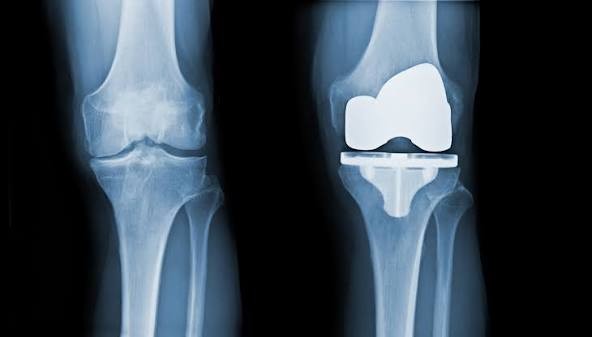

A total knee replacement (TKR) is a surgical procedure that resurfaces damaged knee joint surfaces with metal and plastic components to relieve severe pain and disability, most commonly caused by arthritis. It is typically recommended when other treatments fail to provide adequate relief.

The procedure involves removing damaged bone and cartilage from the thigh bone (femur), shin bone (tibia), and sometimes the kneecap (patella), and replacing them with artificial components. Recovery includes structured physical therapy to restore mobility and strength.

- Resurfacing: The surgeon reshapes the ends of the femur and tibia and resurfaces the underside of the patella using durable metal and plastic implants.

- Components: The artificial knee typically includes a metal femoral component, a metal tibial plate, and a plastic spacer between them, often with a plastic “button” for the kneecap.